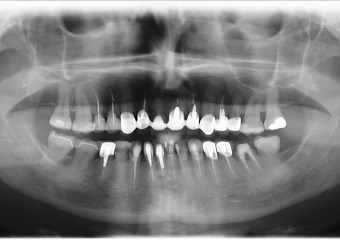

Rx Panorâmico inicial